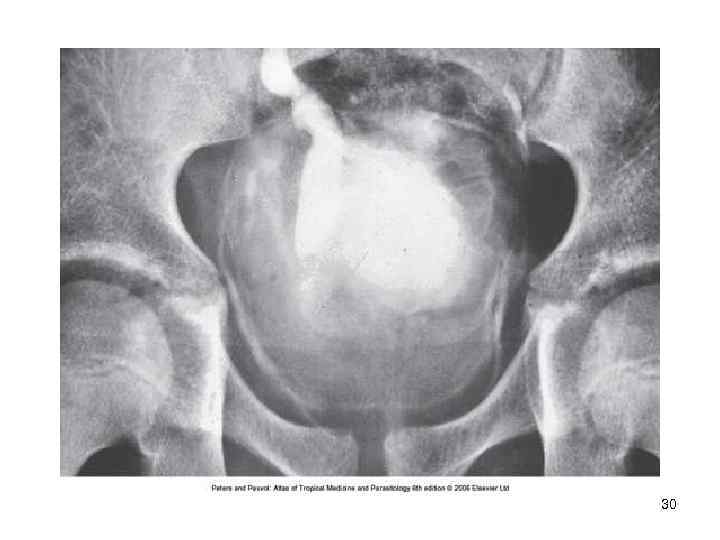

32

Диагностика • Исследование мочи на яйца шистосом после центрифугирования • Максимальное количество яиц выделяется с мочой около 10 -12 часов дня • Интенсивная инвазия оценивается при числе яиц более 50 на 10 мл. мочи • Цистоскопия позволяет выявить изменения на слизистой оболочке мочевого пузыря: гранулемы, » песчаные пятна» . • Эндобиопсия- выявляются яйца S. haematobium • Обзорная рентгенография –обнаруживается обызвествление стенок мочевого пузыря Контрастная урография -изменение структуры мочеточников 33